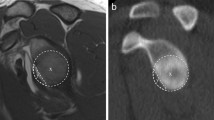

Width and depth of the HSL

The width of the HSL was measured by drawing a line between both of its edges. The depth of the HSL was obtained by placing a virtual circle on the humeral head. The longest perpendicular line from the ground of the lesion to the surface of the circle was defined as the depth of the HSL [12].

This measurement method was performed as recommended by Richards et al. on the transaxial view. A concentric circle was drawn on the humeral head. The centre of the circle was defined as the intersection of the diameter lines, 0 degrees was defined as the anterior edge of the articular surface. Following this method of measurement, the size of the HSL lesion was determined by establishing its location on the humeral head using the circle reference to define an axial frame of 360° (Fig. 1) [37].

A schematic representation of the measurement method according to Richards et al. A best-fit circle is posed on the humeral head. Zero degrees is defined as the anterior edge of the articular surface. The size of the HSL lesion is determined by determining the position of the HSL on the humeral head using the circle reference, which defines an axial frame of 360°

Hall method

The Hall quotient was defined according to Hall et al. on the transaxial view. The HSL was graded according to the percent involvement of the humeral articular surface. An 180° arc was drawn on the humeral articular surface (Fig. 2). Bone loss involving the articular arc was measured. The percentage of involvement of the articular arc was calculated using the following formula: \(\left(\frac{Width of the articular HSL (^\circ )}{180^\circ }\right)*100\) [23].